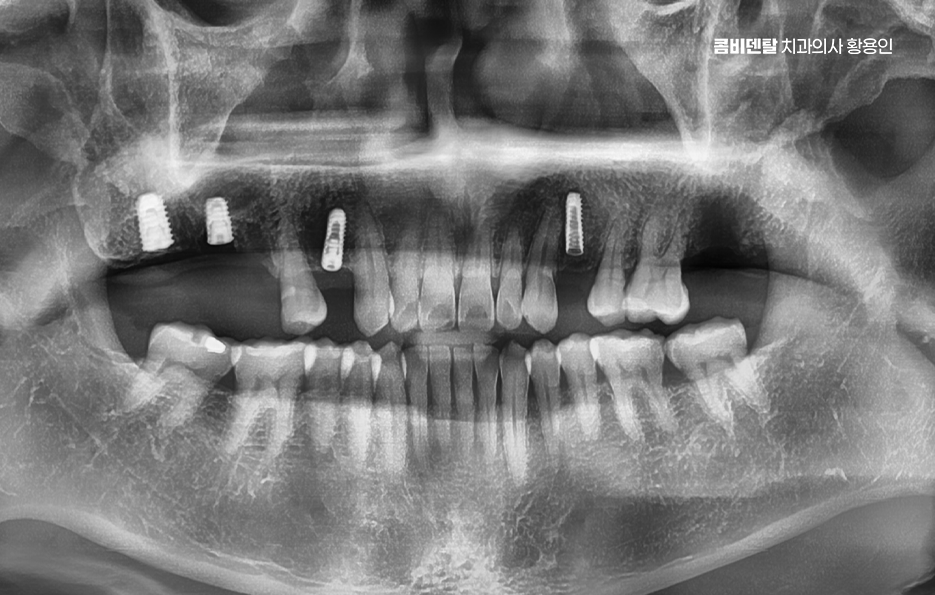

출처 아카이브 열기처음 어금니를 하나 잃었을 땐 그렇게까지 큰일은 아니라고 생각했어요. 충치가 너무 심해서 결국 발치를 하게 됐고, 치과 선생님은 빠진 자리를 임플란트로 채우는 게 좋겠다고 권하셨지만, 솔직히 당시엔 시간도, 돈도 여유가 없었고, 또 막상 하나쯤 없다고 해서 일상이 크게 불편하진 않았기 때문에 그냥 좀 불편하더라도 참자고 마음을 먹었어요. 한쪽으로만 씹는 습관이 생겼지만, 그건 생각보다 쉽게 적응됐고, 어금니 하나 없이도 밥을 먹는 데 큰 무리는 없다는 착각 속에서 점점 그 빈자리에 무뎌져 갔어요. 그렇게 몇 달, 몇 년이 흘렀고, 지금 와서 돌이켜보면 그때 치료를 미뤘던 결정이 얼마나 후회로 돌아오는지 스스로도 놀라울 정도예요. 처음 눈에 띈 변화는 반대쪽 어금니에 가해지는 압력이 점점 커졌다는 거였어요. 무의식적으로 계속 반대쪽만 사용하다 보니 그쪽 치아에 피로가 쌓이기 시작했고, 어느 날부터는 씹을 때 약간의 통증과 불편함이 느껴지기 시작했어요. 그때도 아직은 버틸 수 있다고 생각했어요. 통증이 있긴 해도 일시적일 거라 여겼고, 양치만 잘하면 괜찮아질 거라고 안일하게 넘겼어요. 그런데 문제는 그게 단순한 통증이 아니라 구조적인 불균형에서 시작된 거였다는 걸 늦게 깨달았어요. 빠진 어금니의 빈자리를 그대로 두면서 위쪽의 맞물리던 치아가 점점 내려오기 시작했고, 아래쪽 잇몸에 자극을 주기 시작하면서 잇몸이 자주 붓고 시큰거리는 현상이 생겼어요. 그뿐만 아니라 양옆에 있던 치아들이 빈 공간 쪽으로 기울기 시작하면서 음식물이 자주 끼고, 양치해도 개운하지 않은 날이 많아졌고, 결국 또다시 충치가 생기기 시작했어요. 하나의 치아를 잃은 게 끝이 아니라 주변 치아들까지 도미노처럼 영향을 받기 시작했다는 걸 그제서야 알게 된 거죠. 더 무서운 건 턱관절의 문제였어요.

이처럼 치아 상실 후에 임플란트에 대한 중요성을 느끼게 되는 것은 특히 앞니라면 인상을 좌우하는 위치이기 때문에 미루는 경우가 거의 없지만 어금니의 경우 반대편으로 씹으면 되지 않을까 하면서 치료를 미루는 경우가 많지만 어금니 없으면 얼굴 발음 및 편측 저작으로 인한 반대편 치아의 문제, 잇몸 뼈의 흡수 등 여러 문제로 이어질 수 있는데요

어금니는 단순히 음식을 씹는 역할만 하는 게 아니며 우리 턱과 얼굴을 지탱해주는 일종의 기둥 같은 존재로서 특히 아래 어금니는 턱뼈에 직접 연결되어 있어서 이 부분이 빠지면 턱뼈 자체가 빠르게 흡수되기 시작하고 뼈는 자극이 있어야 유지되는데 어금니가 없어진 자리엔 씹는 자극이 사라지니까 뼈가 점점 가라앉는 거예요.

더 심각한 건 치열 전체가 무너지는 것으로 어금니가 빠지고 그 자리를 비워 두면, 위에 맞물리는 치아가 점점 내려오거나, 옆 치아가 쓰러져 들어가며 이렇게 정출된 치아는 다시 제자리로 돌아오지 않기 때문에, 나중에 임플란트를 하려고 해도 공간이 맞지 않아서 교정치료를 먼저 해야 할 수도 있었어요.

그래서 이런 문제들을 막기 위해서라도 임플란트는 어금니 상실 후 중요한 치료 옵션으로서 임플란트는 빠진 치아의 뿌리 역할까지 해주기 때문에, 단순히 공간을 채우는 게 아니라 턱뼈에 자극을 줘서 뼈 흡수를 막아주고, 위아래 치아가 정상적으로 맞물릴 수 있게 해주며 다른 보철 방식과 비교해도 장기적인 안정성과 기능 회복 면에서 유리한 거예요.

임플란트를 빨리 하는 게 좋은 이유는, 시간이 지나면서 턱뼈가 점점 흡수돼버리면 임플란트를 심을 뼈 자체가 부족해지는 상황이 생기기 때문이며 이때는 뼈이식이나 상악동 거상술 같은 추가 수술이 필요하게 되고, 치료 기간도 길어지고, 비용도 많이 올라가기 때문에 어금니가 빠졌다고 방치하는 시간만큼 치료는 더 복잡해질 수 있다는 점에서 어금니 없으면 얼굴 발음 및 오늘 알아본 것처럼 다양한 문제로 이어질 수 있음을 잘 이해하여 빠르고 나에게 맞는 치료 계획을 세우시고 장기적으로는 수명 유지까지 잘 고려하여 치료 계획을 잘 세워보시길 바라고 있어요